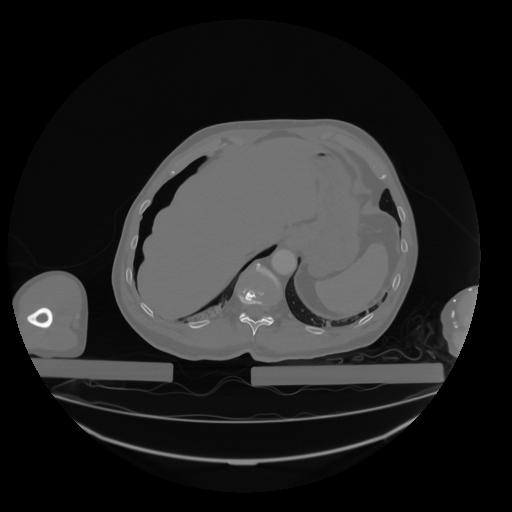

28 CUERPO,CE,Vol,2.0,CUERPO,,